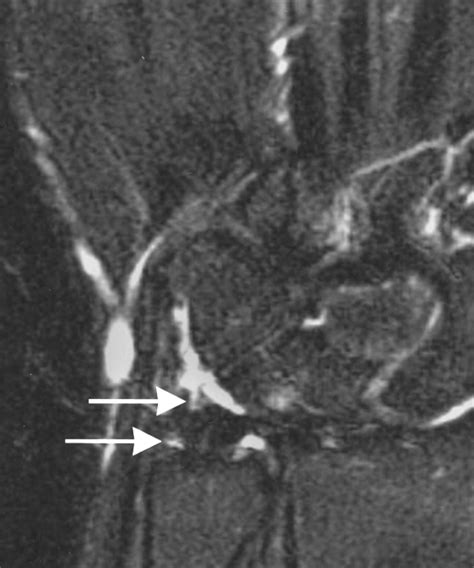

• Imaging Tests: X-rays, MRI, or CT scans may be ordered to visualize the knee joint and confirm the diagnosis. MRI is particularly useful for detecting soft tissue injuries like cartilage tears.